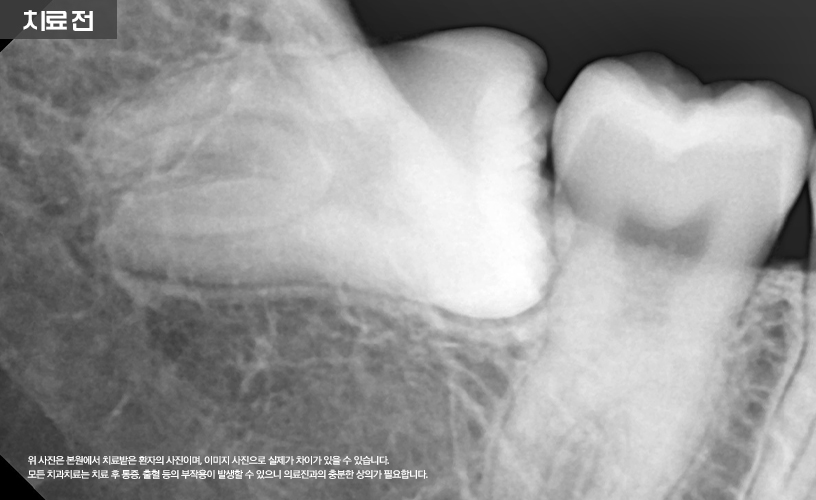

상기 환자분은 하악 매복 사랑니로 인해

본 원에서 발치한 사례입니다.

환자분의 경우 하악에 매복된 상태로 있는

사랑니를 확인할 수 있습니다.

특히 #48번 사랑니의 경우

파노라마에 하치조 신경과 겹쳐 보여

CT 촬영을 통해 자세한 검진이 필요합니다.